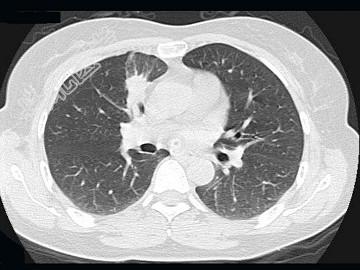

- 单项选择题女,52岁, 头晕2周,MRI检查如图, 最可能的诊断为 ( )

D、脑内多发转移瘤